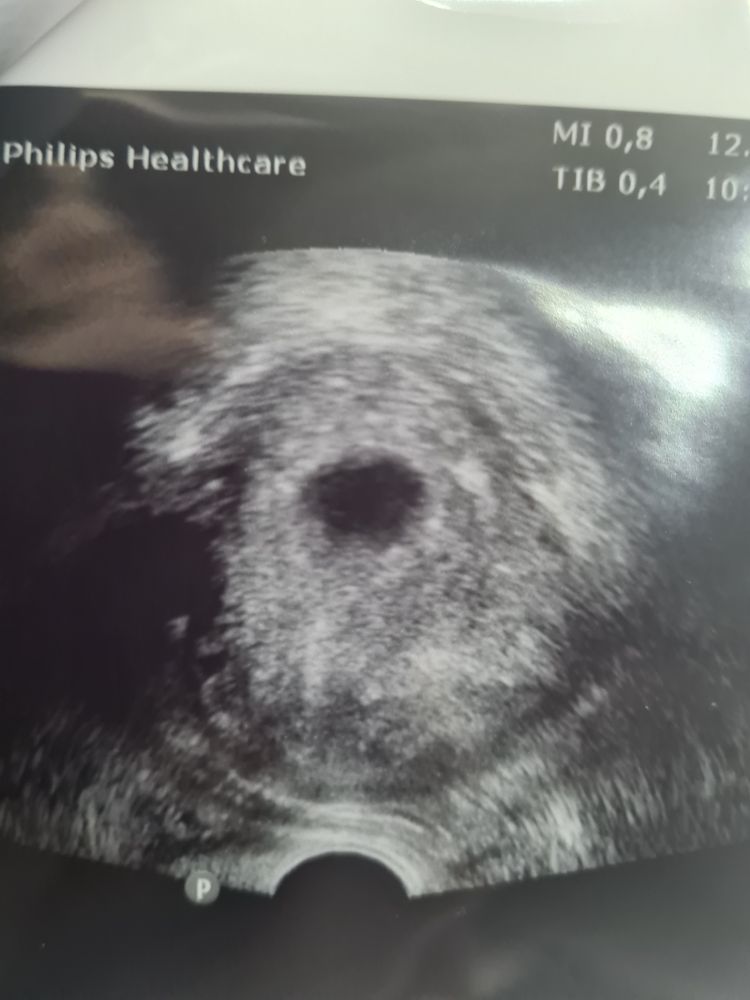

Poppiholla, незнаю .мы не изменяли его ,просто увидели пя и все сказал через неделю прийти . Изображение Есть только такое фото

Не исключает, к сожалению. Что с размерами ПЯ?

Viktoria , но, на 29 день уже должно быть СБ+. А у вас даже желточного мешка нет.

Grape, узи было вагинальное . Но смотрели быстро . Увидели пя и все .